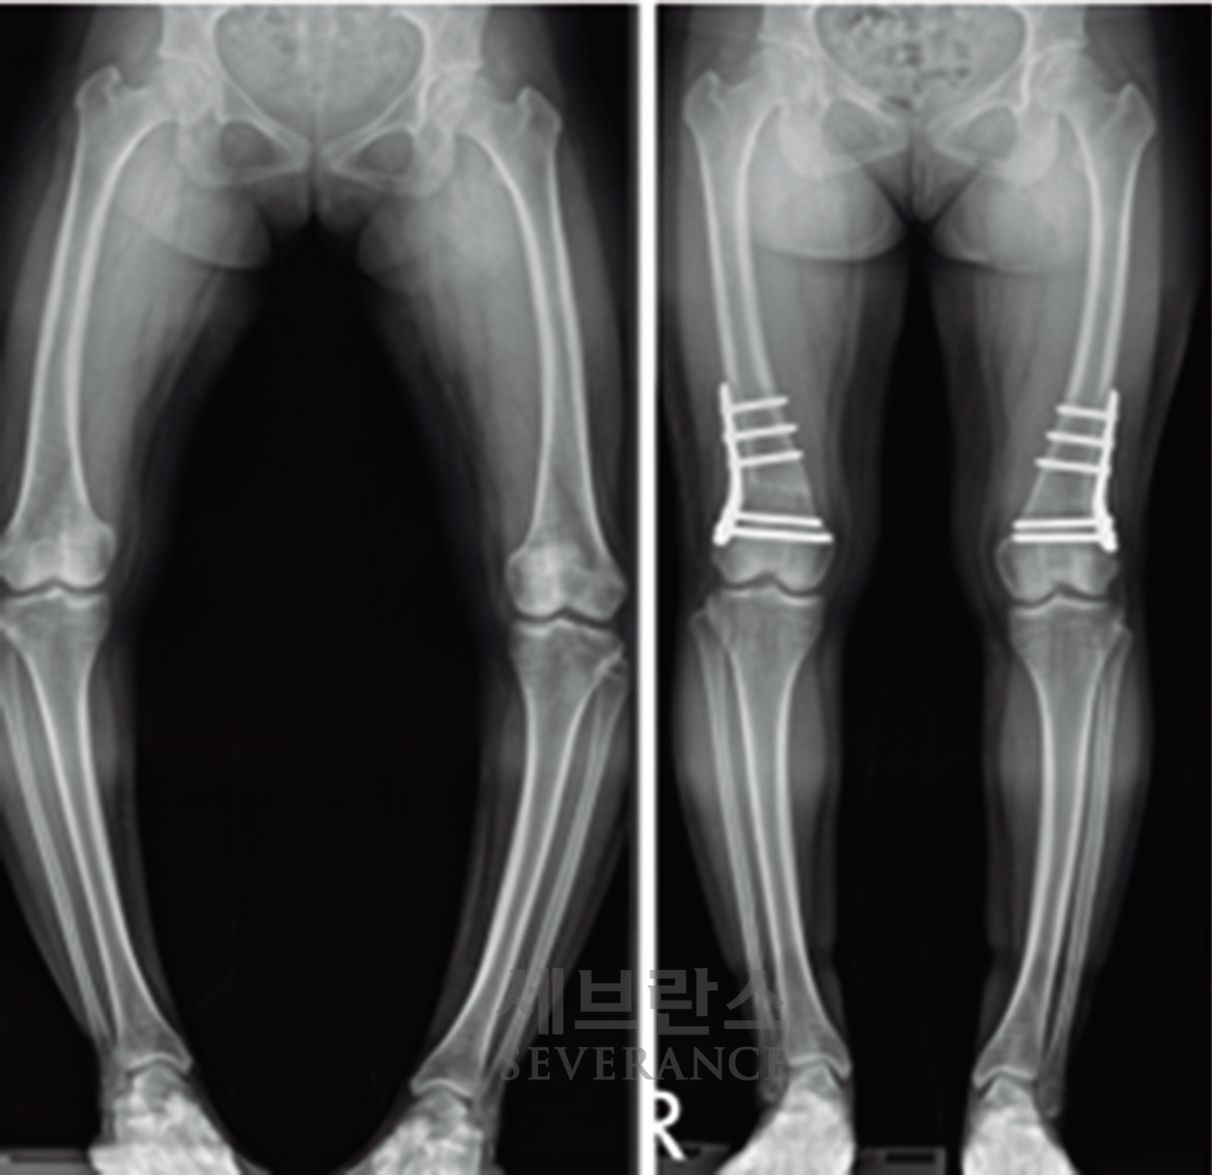

- 성장조절술

성장판이 열려 있는 아이에게 많이 사용되는 성장조절술은 한쪽 성장판의 성장을 일시적으로 억제해 시간이 지나면서 다리 길이나 각도가 서서히 교정되도록 하는 방법입니다. 일반적으로 심하지 않은 O다리나 X다리, 경미한 다리 길이 차이에 적용합니다. 흉터가 작고 회복이 빠르지만, 효과가 나타나기까지 시간이 필요하고 성장이 끝난 아이에게는 사용할 수 없습니다. 또 교정이 완료된 후에도 성장 과정에서 일부 각도가 다시 돌아오는 ‘성장 반동’ 현상이 나타날 수 있습니다. 따라서 성장판이 완전히 닫힐 때까지 정기적으로 추적 관찰을 받아야 합니다.

특발성 대사성 질환으로 인한 외반슬(X다리)에서 성장조절술을 시행한 환아성장판